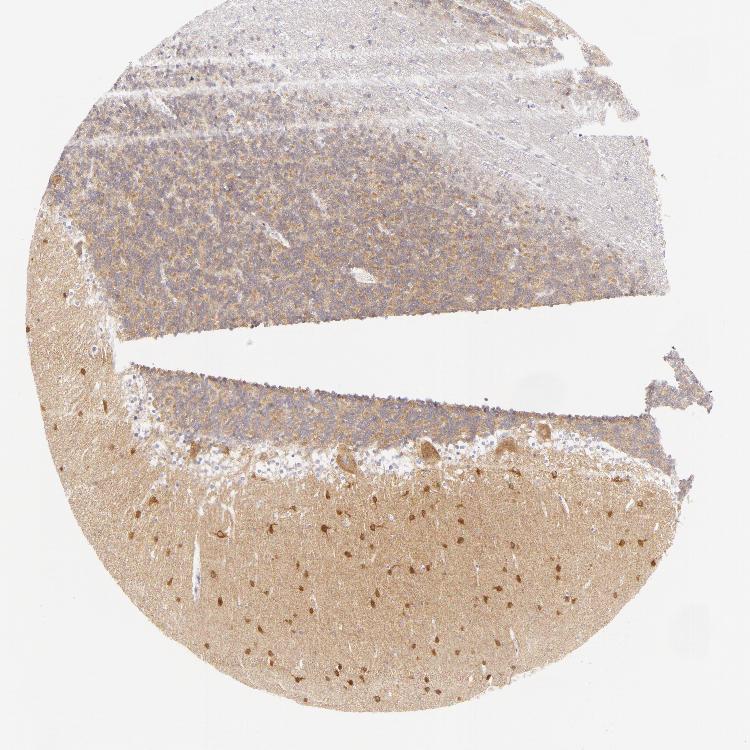

CEREBELLUM - Antibody stainingi

Antibody staining in the annotated cell types in the current human tissue is reported as not detected, low, medium, or high, based on conventional immunohistochemistry profiling in selected tissues. This score is based on the combination of the staining intensity and fraction of stained cells.

Each image is clickable and will lead to virtual microscopy that enables deeper exploration of all samples and also displays staining intensity scores, fraction scores and subcellular localization as well as patient and tissue information for each sample.

Antibody HPA010122Antibody HPA071006Antibody CAB001999Antibody CAB002000

Purkinje cells MediumNot detected-High

Cells in granular layer Not detectedMedium-Medium

Cells in molecular layer HighHigh-High